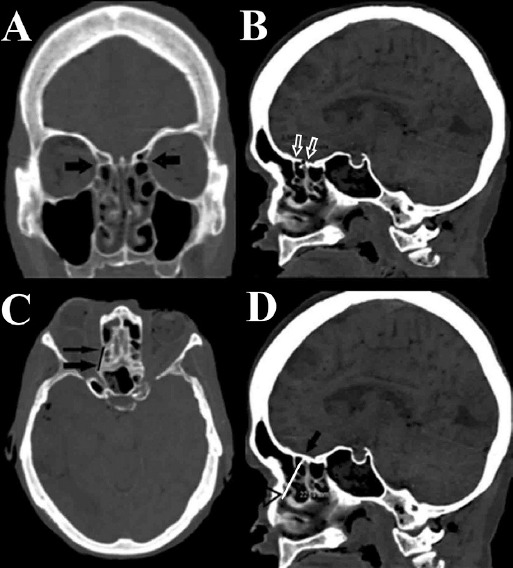

Method: Five fresh frozen cadaveric heads underwent computed tomography and endoscopic sinus surgery. The lateromedial length of the anterior ethmoidal artery (AEA) and its distance to the axilla of the middle turbinate (MTA), the sphenoethmoidal recess (SR) and the posterior ethmoidal artery were measured. The posterior ethmoidal artery (PEA) was referenced to the SR. These anatomical parameters were measured both radiologically and endoscopically, and the compatibility of the two was examined.

Results: Ten nasal cavities were dissected. We found that the distance of MTA to the AEA was 16±8 mm in dissection, 21±4 mm radiologically in the sagittal section, the distance of SR to the AEA was 14±3 mm in dissection, 19±4 mm radiologically in the sagittal section, and the distance of the AEA to the PEA was 10±3 mm in dissection, 12±3 mm radiologically in the axial section. The distance of the PEA to SR was 6±3 mm in dissection, 8±2 mm radiologically in the sagittal section.

Conclusions: The distance of the AEA to the MTA, the distance of the AEA to the PEA and the distance of the PEA to the SR were compatible with each other in the dissection and in the radiologically evaluation, whereas the distance of the AEA to the SR was not compatible.